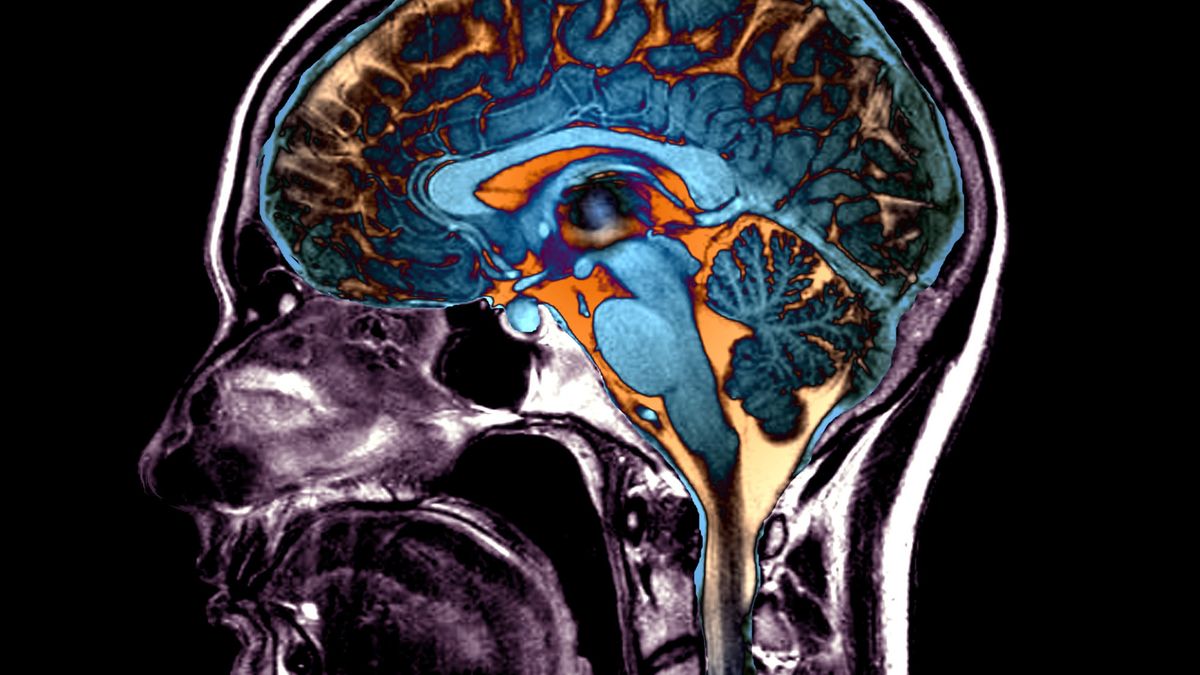

Półkule mózgu